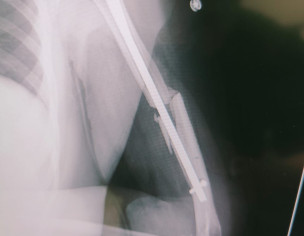

Asalamwalikum last year 11 july ko husband ka accident ma fracture howa tha right hand 12 ko doctor na operate kar ka rod dal diya iska bad wrist down hai still abhi tk fracture heal nahi howa hai wrist down hi hai last 3 months sa brace bhi lagaya howa hai but no improvment as such kindly guide us what to do

this is radial nerve palsy aap Karachi ki hn

please visit any orthopedics surgeon, any senior one .. the bone is not properly alined and radial nerve compression occur